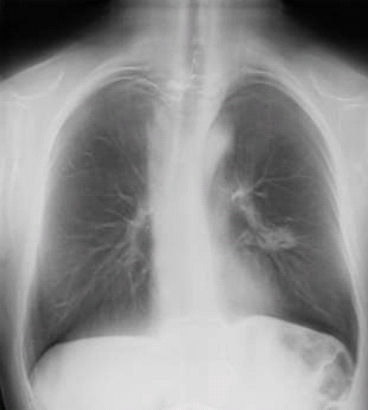

Digital chest tomosynthesis uses an upgraded DR system with a panning tube head. Image courtesy of Dr. Luca Bertolaccini.

Digital chest tomosynthesis uses an upgraded DR system with a panning tube head. Image courtesy of Dr. Luca Bertolaccini."Although it lacks the depth resolution of CT, tomosynthesis provides some of the benefits of CT at lower costs and radiation dosages," wrote lead author Dr. Alberto Terzi, of S. Croce City Hospital in Cuneo, and colleagues. "Furthermore, digital chest tomosynthesis is less expensive than CT at approximately one-sixths of the cost of a CT" (JTO, June 2013, Vol. 8:6, pp. 685-692).